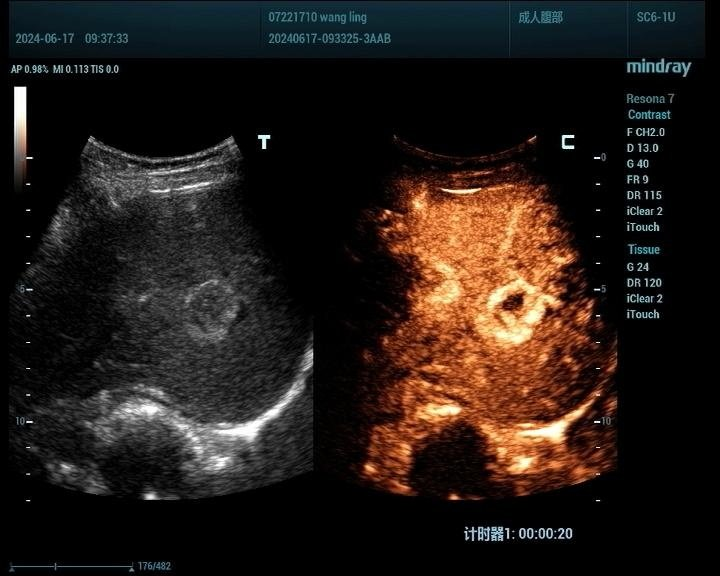

肝脏肿瘤分为良性和恶性,其中血管瘤是最常见的肝脏良性肿瘤,肝癌是最常见的恶性肿瘤。肝脏肿瘤超声影像诊断方面主要有肿瘤病灶的检出、对已检测肿瘤的定性诊断、肝局灶性病灶中肿瘤与非肿瘤病变的鉴别。超声造影对肝脏肿瘤的鉴别诊断主要是通过增强和动态增强方式观察肿瘤。

肝癌病例2